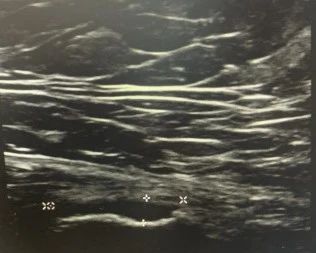

肌骨超声通过高频超声扫描产生临床图像,帮助医生清晰分辨肌肉、韧带、关节、神经等组织层次关系、结构纹理等,获取这些组织的炎症、创伤、病变等信息。这种分辨甚至可以达到毫米级以下。

以肌肉组织为例。运动爱好者常说的肌肉,一般指的是骨骼肌,由肌纤维构成。每条肌纤维外面都包裹有一层薄的结缔组织膜,称为肌内膜。多条肌纤维构成一束肌肉,外面由结缔组织包裹,称为肌束膜。多条肌束构成整块肌肉,其外包裹的组织,称为肌外膜。相邻的肌肉之间,由筋膜分隔,称为肌间隔。将肌肉连接在骨骼关节处粗硬的无弹性的纤维状组织束,称为肌腱。

肌内膜、肌束膜、肌外膜、肌间隔、肌腱等这些连接处,全都是运动损伤的好发部位。借助肌骨超声,医生就可以精准找到患者“痛点”,为下一步诊疗做好准备。

最后,与您分享今年7月德尔康尼通过肌骨超声检查发现的部分损伤病例。

左小腿腓肠肌内侧头损伤